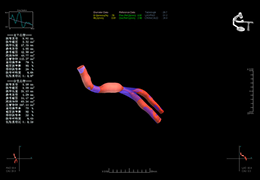

ANYTHINK 经导管主动脉瓣膜置换术分析系统